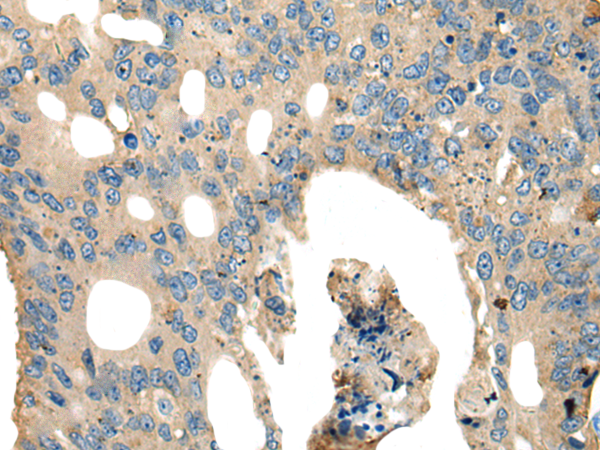

分类: 科研抗体货号: P02456别名: SHK; CARKL应用: WB,IHC反应种属: Human, Mouse

分类: 科研抗体货号: P02504别名: FHR2; HFL3; CFHL2应用: WB,IHC反应种属: Human

分类: 科研抗体货号: P02498别名: CEN3; CDC31应用: WB,IHC反应种属: Human, Mouse

分类: 科研抗体货号: P02487别名: HEPP; SEI-3/HEPP应用: WB,IHC反应种属: Human

分类: 科研抗体货号: P02561别名: ER1; MI-ER1应用: WB,IHC反应种属: Human, Mouse

分类: 科研抗体货号: P02481别名: 4F2; CD98; MDU1; 4F2HC; 4T2HC; NACAE; CD98HC应用: WB,IHC反应种属: Human

分类: 科研抗体货号: P02557别名: CRN7; POD1; 0610011B16Rik应用: WB,IHC反应种属: Human, Mouse, Rat

分类: 科研抗体货号: P02473别名: CPR4应用: WB,IHC反应种属: Human